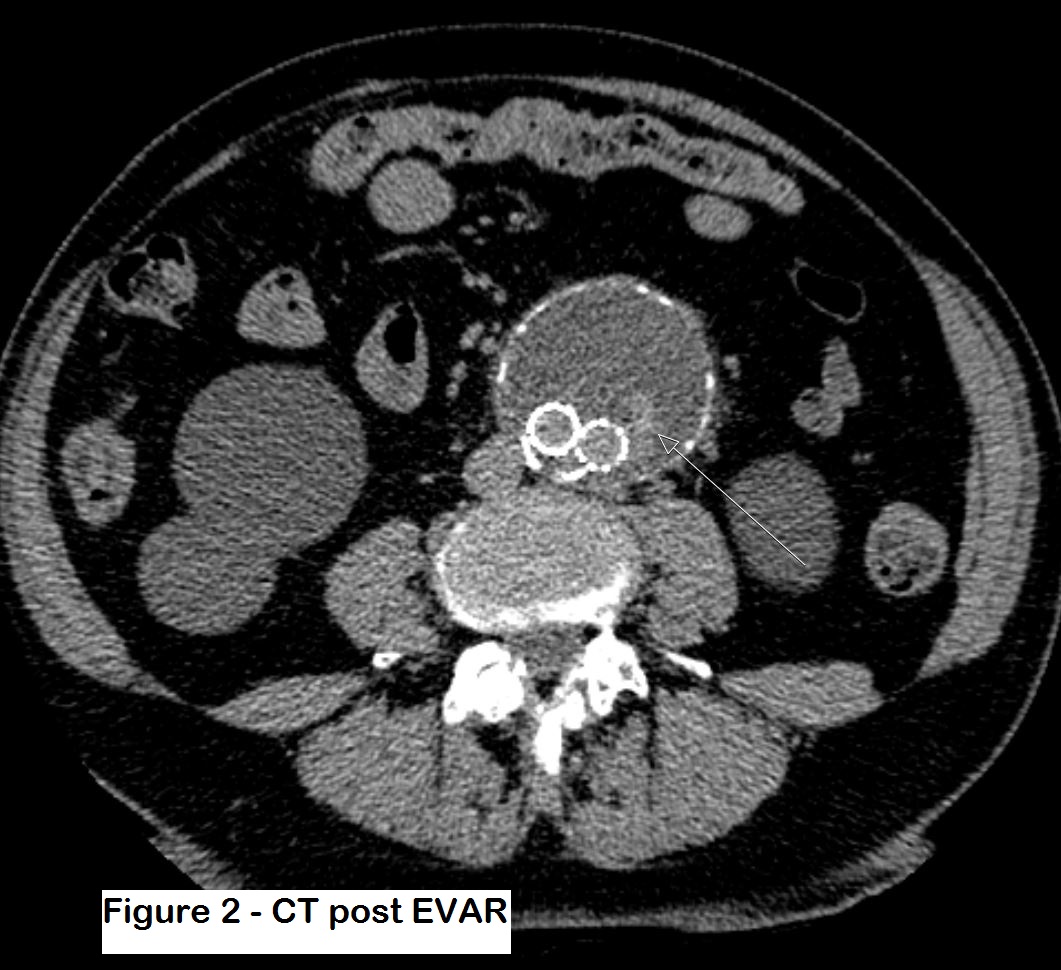

Figures 1 and 2: Post-op CT which shows some contrast within the aneurysm sac but it is difficult to ascertain the type of leak. The patient was thus referred for an ultrasound study.

No endoleak was noted during the intervention, but at the first CT follow-up a month later, there was a suspected endoleak. It was however difficult to ascertain whether this was a type 1 or type 2 leak. The patient also had impaired renal function after the procedure, so further use of iodinated contrast was considered to be inappropriate. Therefore, a contrast enhanced ultrasound study (CEUS) was performed instead to see if it could determine the type of endoleak.